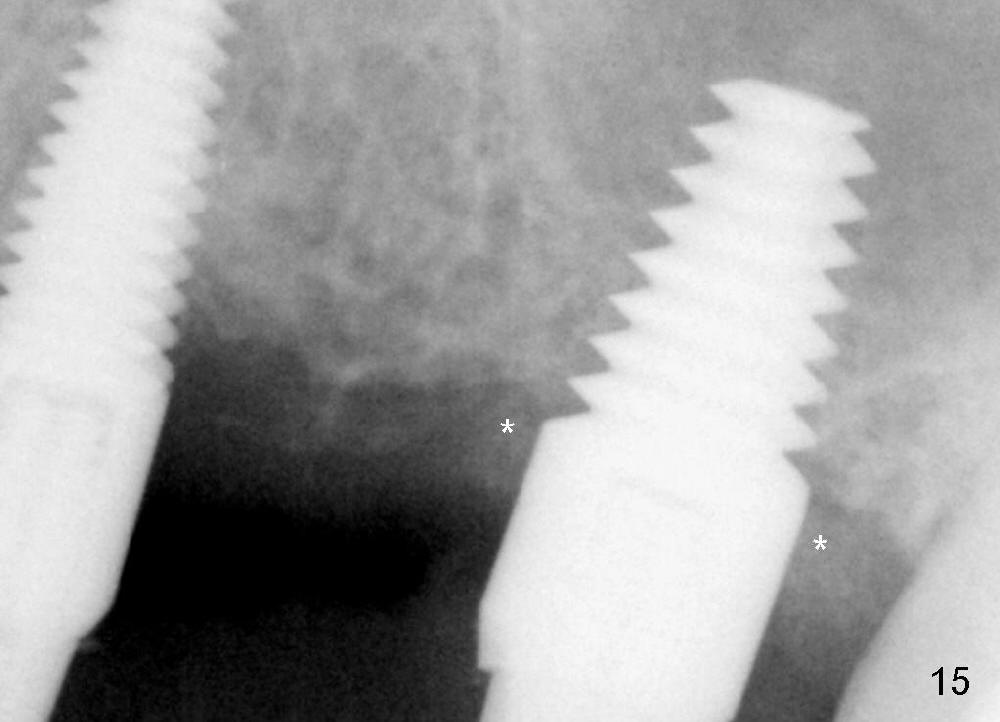

Two PAs are taken 5 months postop (Fig.15,16). Patterns of bone graft (*) between these PAs are different, which suggests presence of the graft buccal to the implant at the site of #14. Another piece of evidence of the graft is that the buccal socket heals (Fig.17 B) without implant thread exposure (Fig.19). These two implants are ready for definitive restoration (Fig.18-20). Fig.21 shows the final restoration 5 months post cementation.